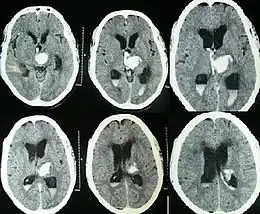

Intraparenchymal hemorrhage can be recognized on CT scans because blood appears brighter than other tissue and is separated from the inner table of the skull by brain tissue. The tissue surrounding a bleed is often less dense than the rest of the brain because of edema, and therefore shows up darker on the CT scan.[30] The oedema surrounding the haemorrhage would rapidly increase in size in the first 48 hours, and reached its maximum extent at day 14. The bigger the size of the haematoma, the larger its surrounding oedema.[31] Brain oedema formation is due to the breakdown of red blood cells, where haemoglobin and other contents of red blood cells are released. The release of these red blood cells contents causes toxic effect on the brain and causes brain oedema. Besides, the breaking down of blood-brain barrier also contributes to the odema formation.[13]